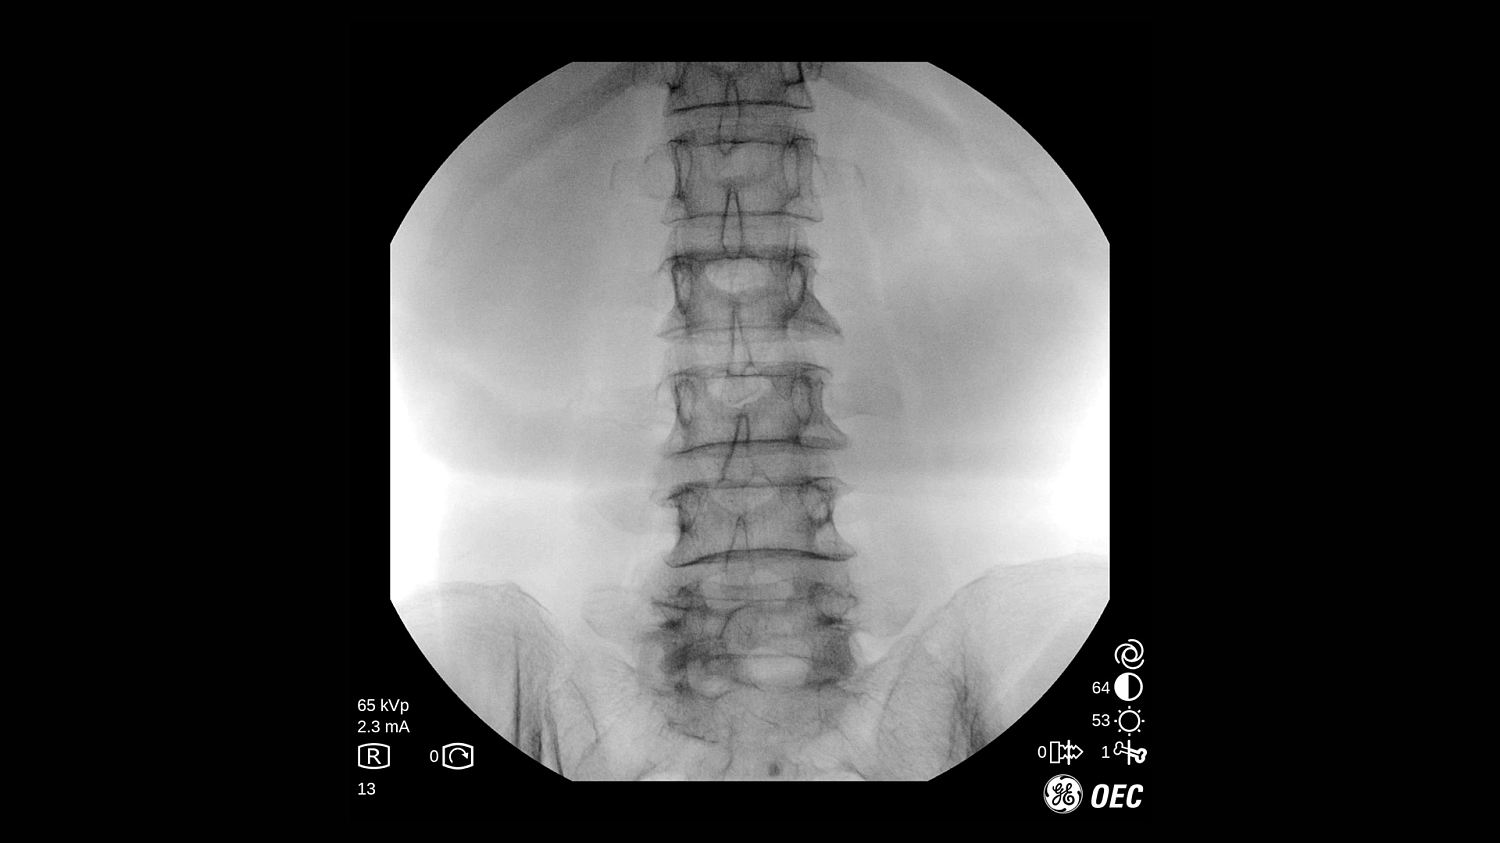

GE Healthcare OEC One CFD относится к классу мобильных рентгеновских аппаратов с С-образной дугой, в которых все ключевые узлы — излучатель, детектор, монитор и панель управления — объединены в единую компактную конструкцию. КМОП-плоскопанельный детектор и фирменная цепочка обработки Clear View обеспечивают высокую детализацию изображения в широком спектре клинических задач: от рутинных травматолого-ортопедических вмешательств до эндоваскулярных процедур и сложной спинальной хирургии. Интеллектуальные алгоритмы подавления помех от металлоконструкций, автоматической оптимизации окна и уровня, а также режимы увеличения позволяют уверенно визуализировать мелкие структуры, проводники и импланты без существенного роста дозовой нагрузки.

- Специализированные клинические профили для ортопедии, спинальной хирургии, общей хирургии, урологии, сосудистых и болевых процедур.

| Низкодозовая рентгеноскопия | Снижение лучевой нагрузки при длительных рентгеноскопических исследованиях и повторных проверках положения имплантов. |

| Импульсная рентгеноскопия | Формирование изображения серией импульсов для уменьшения дозы при сохранении достаточной детализации. |

| Режим цифрового снимка (Digital Spot) | Получение высокодетализированного статического кадра для оценки критически важных анатомических структур. |